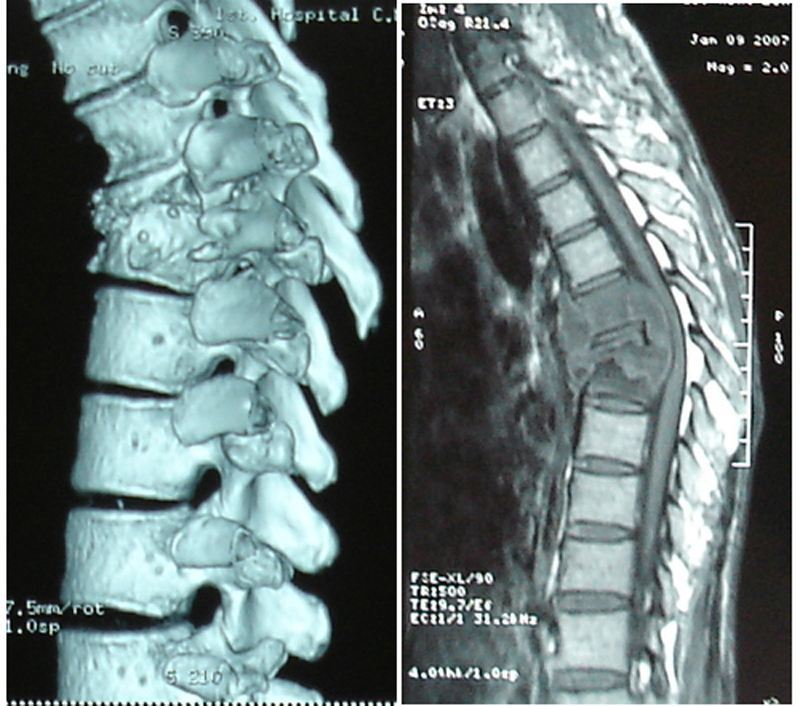

腰椎分離症・分離すべり症の基礎知識 point 腰椎分離症・分離すべり症とは 腰椎の変形によって腰痛や背中の痛みを起こす病気のことです。脊椎分離症(本来くっつている脊椎が離れてしまっている病気)が原因のことが多いです。腰椎分裂症やすべり症と同様、高齢者に多く見られるのがこの変形性腰椎症です 腰椎症とも呼ばれていますが、聞きなれない人も多くいるかもしれませんね それは、腰が痛くても、年齢のせいだと諦めている人が多いからではないでしょうか Eo健康 エクササイズ「腰痛改善」:腰は運動の中心腰椎分離症(腰椎分離すべり症) 腰椎分離症とは? 腰椎の後方支持要素である椎弓が分離(骨折)している状態を分離症といいます。 10才代前半から思春期にかけてスポーツを行っていた人に好発するといわれています。 第5腰椎に発生することが多く

このページでは、当院で行っている成長期の腰椎分離症の治療成績と、その後の経過をお伝えいたします。 腰椎分離症の治療は大きく分けて2つあります。 1つは分離した部分を骨癒合させる方法。 もう1つは、分離した部分の癒合が期待第五腰椎分裂(分離?)症 日時: 2258 名前: うさこ 約2週間前に突然腰が痛くなり、冷房の効いた室内での長時間のデスクワークがたたったのだろうと、1週間報知したのですが、一向に良くならなかったので、どうにかしないと!と思ったのですが、病院へ行っている時間がなかった 腰椎分離症の筋トレの効果 腰椎分離症とは椎弓と呼ばれる腰椎の後方部分が分離した状態のことです。 成長期のスポーツ選手に多く見られる腰痛の症状の一つで、 ジャンプや腰の回旋を行うことで腰椎に負荷がかかり疲労骨折などが原因で亀裂が入ることで起こります。